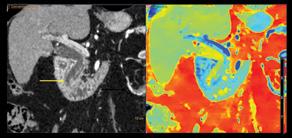

În cadrul Centrului de Imagistică al UMF Craiova, folosim deja soluții bazate pe IA în activitatea zilnică, ceea ce demonstrează aplicabilitatea practică a acestor tehnologii. Spre exemplu, în portofoliul experienței noastre se numără programe de IA capabile să analizeze atât achiziții CT, cât și IRM. Astfel, dispunem de un software de IA specializat în

analiza CT-ului toracic, care detectează automat nodulii pulmonari și îi evidențiază vizual direct în cadrul investigației. În plus, algoritmul generează un raport detaliat ce include localizarea exactă a fiecărui nodul, dimensiunile liniare (diametrele), volumul, precum și un scor de suspiciune oncologică. <figura 1> De asemenea, software-ul furnizează recomandări standardizate de follow-up, conform ghidurilor actuale, facilitând astfel o abordare mai rapidă, precisă și uniformă a cazurilor. Prin aceste funcționalități, AI-ul sprijină radiologul în depistarea precoce a leziunilor, reducând riscul de omisiuni și contribuind la o stratificare mai adecvată a riscului pacientului.